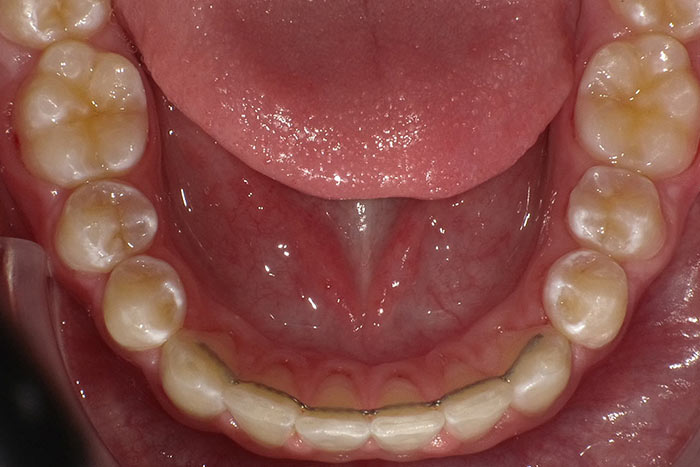

Dauerretainer

Ein Dauerretainer im vorderen Bereich von Ober- und Unterkiefer ist äusserst wichtig!

Durch Einkleben eines innenliegenden dezenten Bogens hinter den Schneidezähnen ist ihre Position gesichert und die Zähne können in den allermeisten Fällen nicht zurückwandern. Das Material des Bogens besteht aus einer geschmacksfreien und mundverträglichen Edelmetalllegierung. Befestigt wird er durch grazile Klebepunkte. Beim Sprechen und Essen stört er nicht und ist von vorne unsichtbar.

Darüberhinaus ist zur Stabilisierung des gesamten Zahnbogens das nächtliche Tragen von Retentionsschienen notwendig.